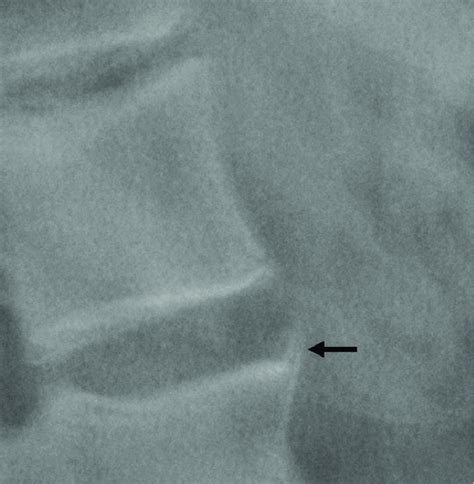

Finally, let’s talk about syndesmophytes . In pathology, particularly in the context of rheumatology and radiology, a syndesmophyte refers to a bony growth or calcification within a spinal ligament, specifically the outer fibers of the annulus fibrosus of the intervertebral disc. These bony growths are characteristically seen in certain types of inflammatory arthritis, most notably ankylosing spondylitis. They appear on X-rays as thin, vertical bony bridges connecting adjacent vertebrae. Unlike osteophytes, which are bony spurs that grow horizontally from the vertebral bodies, syndesmophytes grow vertically and are typically thinner and more delicate. They are a hallmark of axial spondyloarthritis and play a crucial role in diagnosing and monitoring the progression of the disease.

Radiologists play a crucial role in identifying syndesmophytes and differentiating them from other types of bony growths. The appearance of syndesmophytes on X-rays is often described as “marginal,” meaning that they originate at the edges of the vertebral bodies and extend vertically along the spine. This is in contrast to osteophytes, which are typically larger, more irregular in shape, and grow horizontally from the vertebral bodies. The distribution of syndesmophytes can also provide clues to the underlying diagnosis. In ankylosing spondylitis, syndesmophytes typically involve the entire spine, from the cervical to the lumbar region. However, in other conditions, such as psoriatic arthritis, syndesmophytes may be more patchy and asymmetrical.